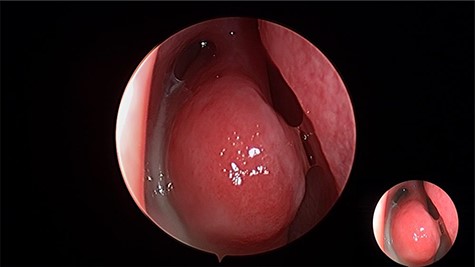

Endoscopic removal of the ectopic molar tooth (Fig. 3) along with dissection and removal of both cysts. With the help of different angled endoscopes and forceps.

Intraoperative endoscopic view of ectopic tooth and the cyst, the patient’s symptoms were resolved completely postoperatively and remained symptoms free for 4 years follow-up